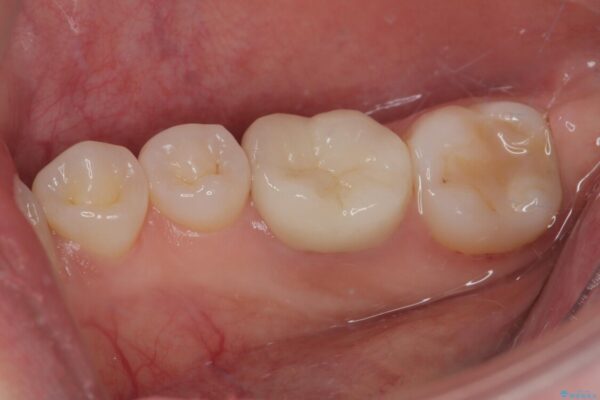

その後、ファイバーコア(グラスファイバー製の支台)を築造し、最終的には精密な適合性と審美性に優れたオールセラミッククラウンによる補綴をしました。

このセラミッククラウンは、歯科技工士と連携し、1本1本の形・色・噛み合わせまで細部にこだわって製作しており、見た目の自然さだけでなく、長期的に安心して噛める機能性も重視しています。

• ラバーダム使用で再感染リスクを抑えた再根管治療+精密な補綴による長期安定を実現 治療後画像